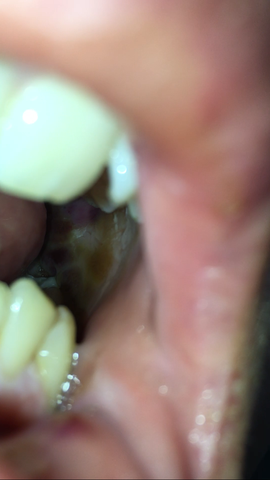

Eitrige Locher Nach Weisheitszahn Op Ist Es Entzundet Schmerzen Operation Zahne